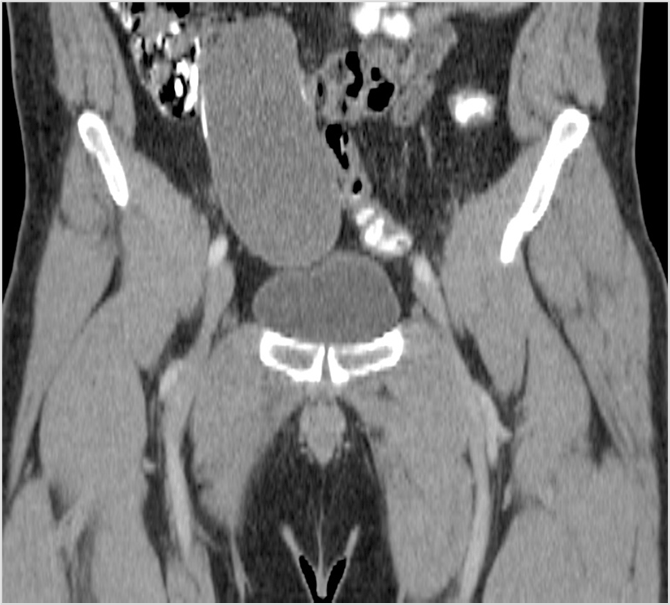

This condition was seen in this recently postpartum 28 year old woman who has pelvic pain.

What is osteitis condensans ilii?